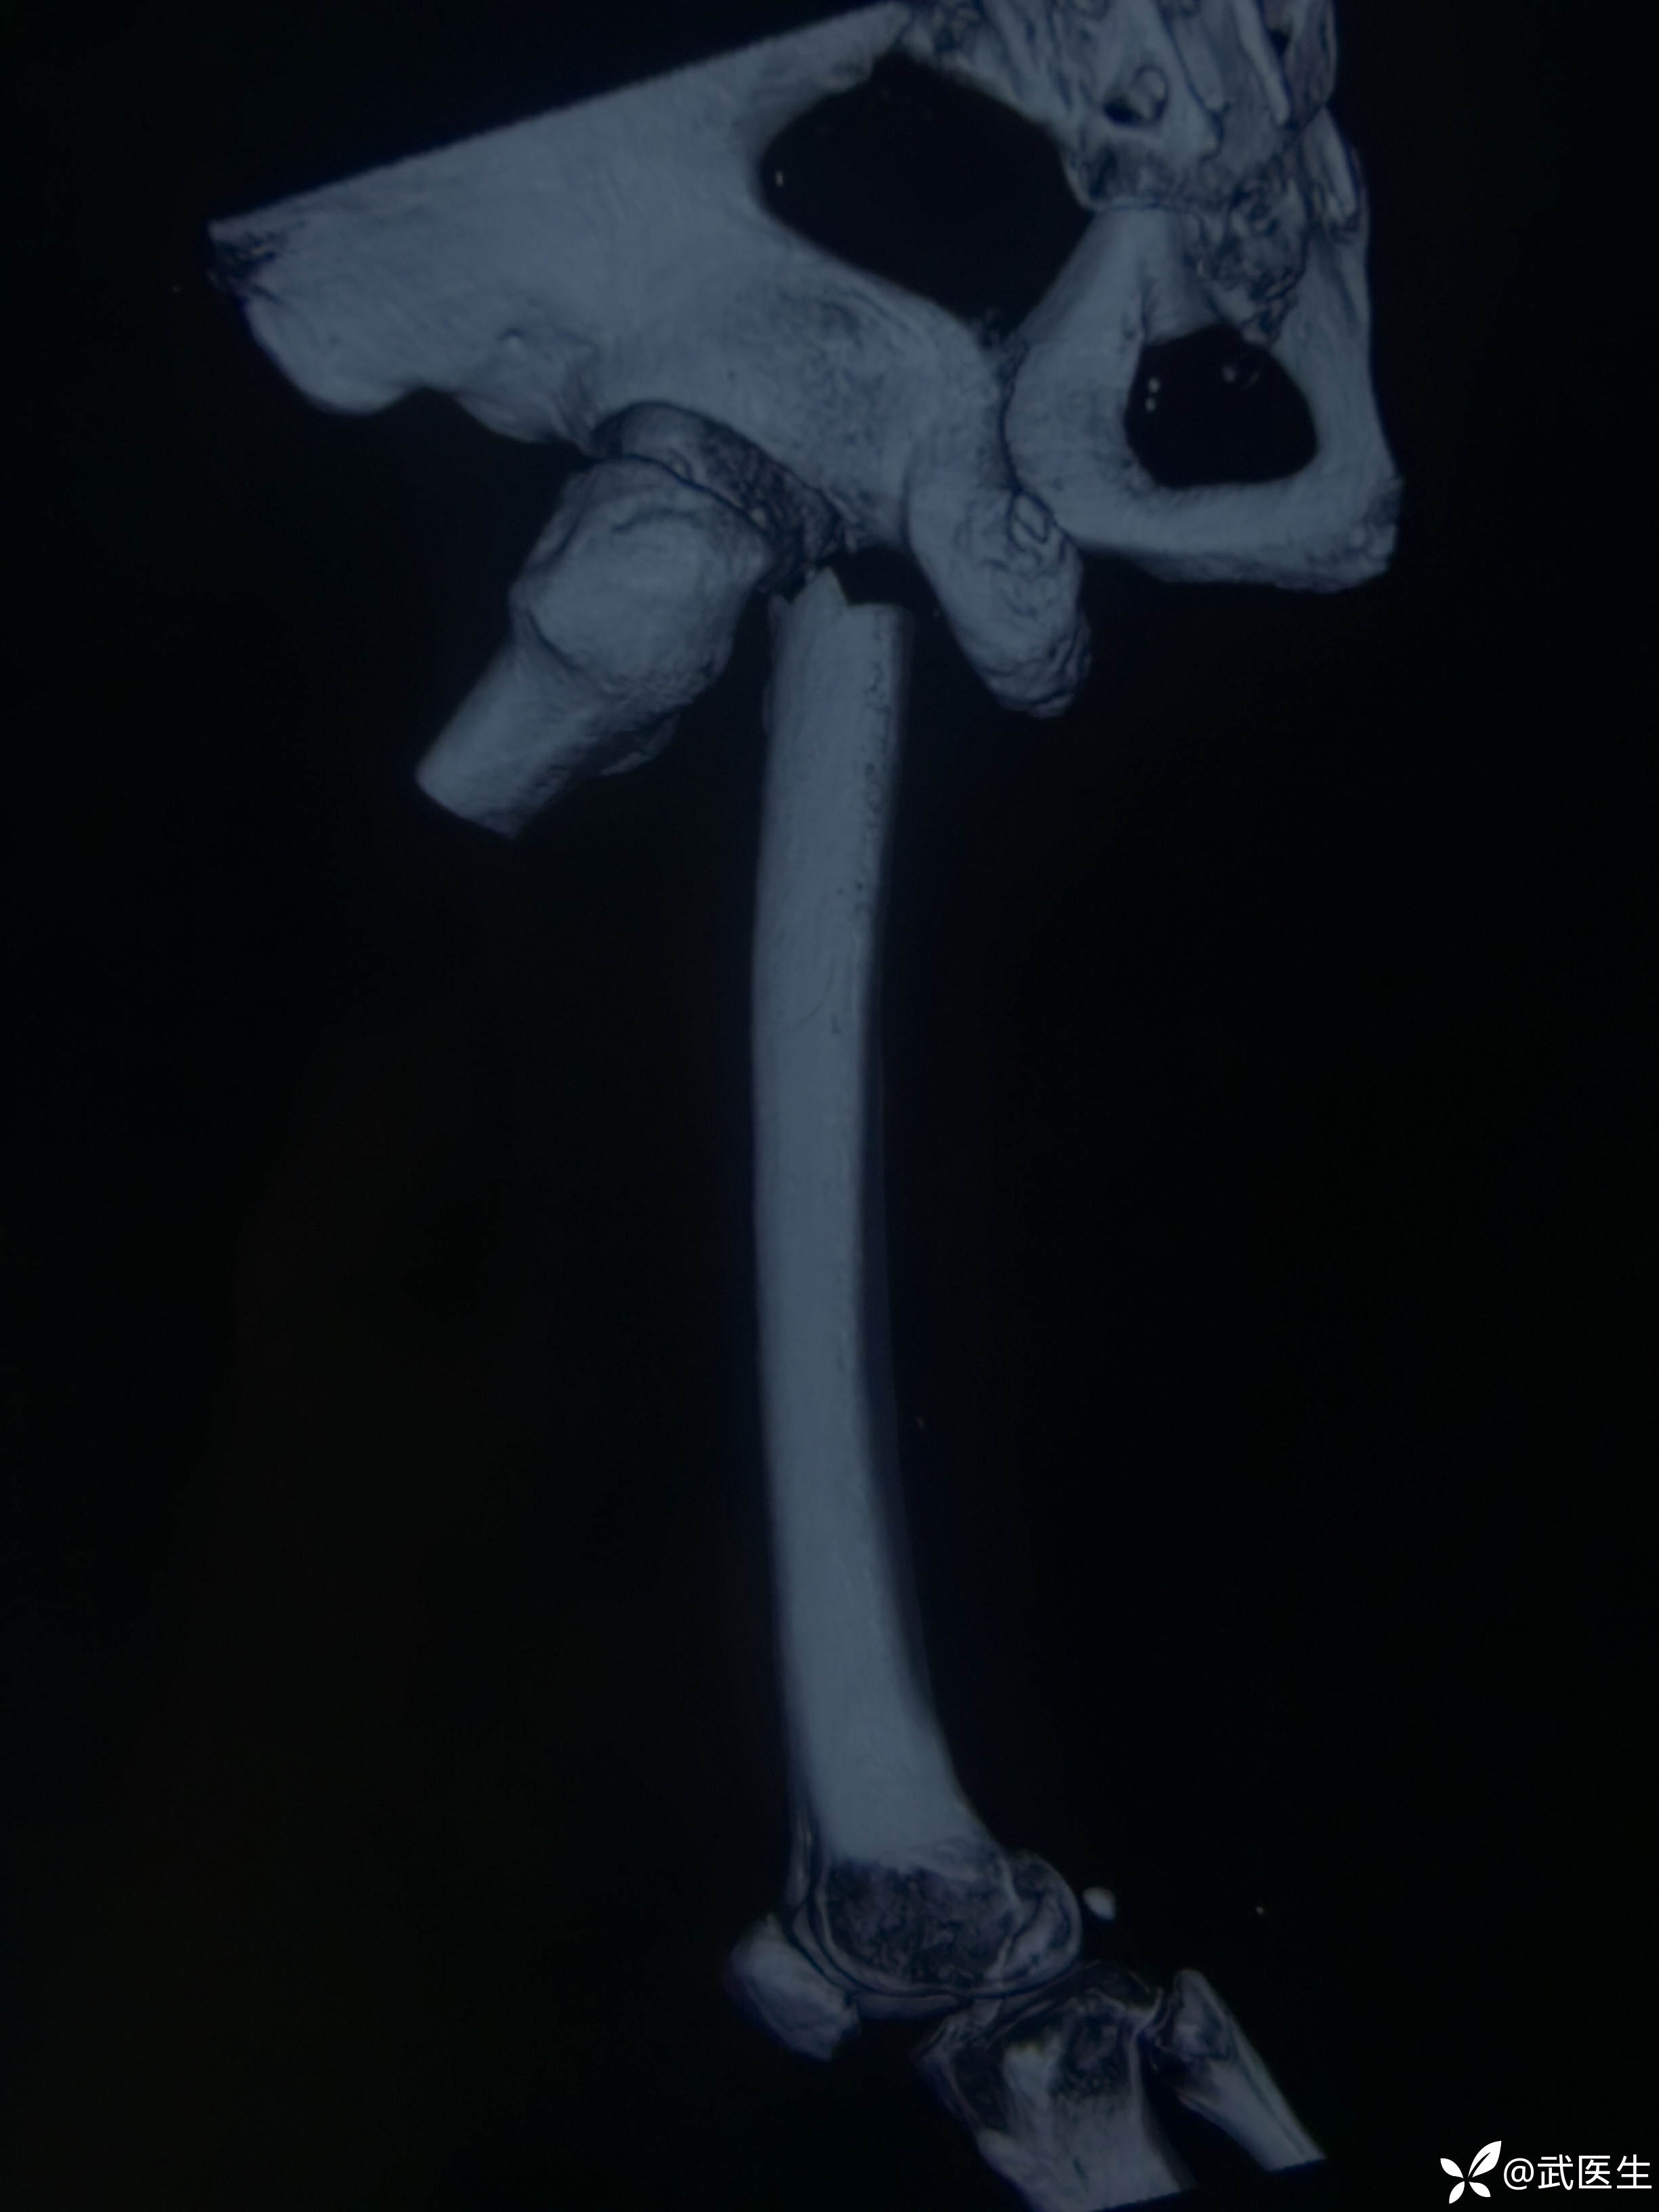

分享一例髓内钉治疗股骨近端骨折病例

男,66岁,摔伤致左大腿疼痛活动受限三小时就诊,门诊以“左股骨干骨折”为诊断收住入院,上图

股骨近端骨折,老先生挺瘦,很奇怪的是,大腿几乎无肿胀,入院后骨牵引,老先生也没怎么感觉骨折部位特别疼痛。